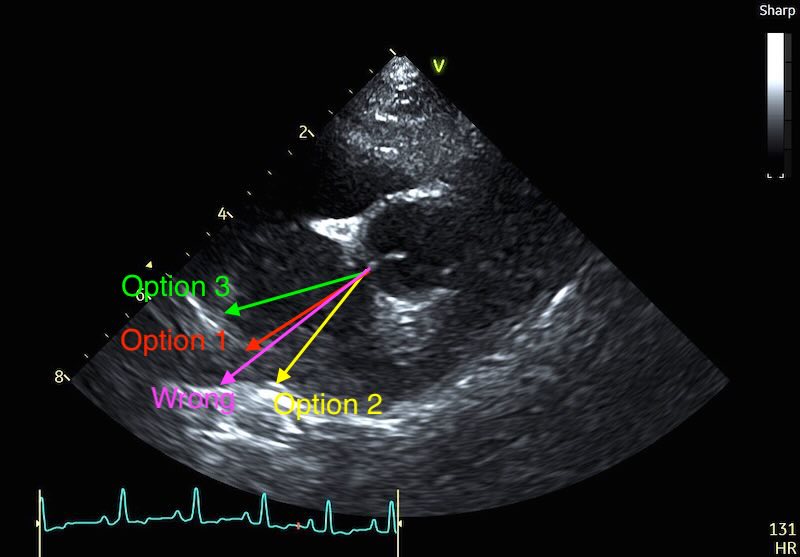

The Clinical Workaround: If you see a vein entering the atrium, do not measure into the vessel. There are multiple described approaches for coping with this, and as yet no consensus on the best approach:

- Option 1: “approximate” the atrial border by connecting the visible edges of the atrium with an imaginary curved line that follows the natural contour of the chamber. If the dropout is so severe that you are guessing, it is time to move to a different view.

- Option 2: Angle your measure to the little ‘bump’ that sits just to the right of the vein.

- Option 3: Angle your measure to the wall where it first becomes visible to the left of the vein

Personally, I’m a fan of option 2. But set guidelines if published will maybe solve this debate for good…